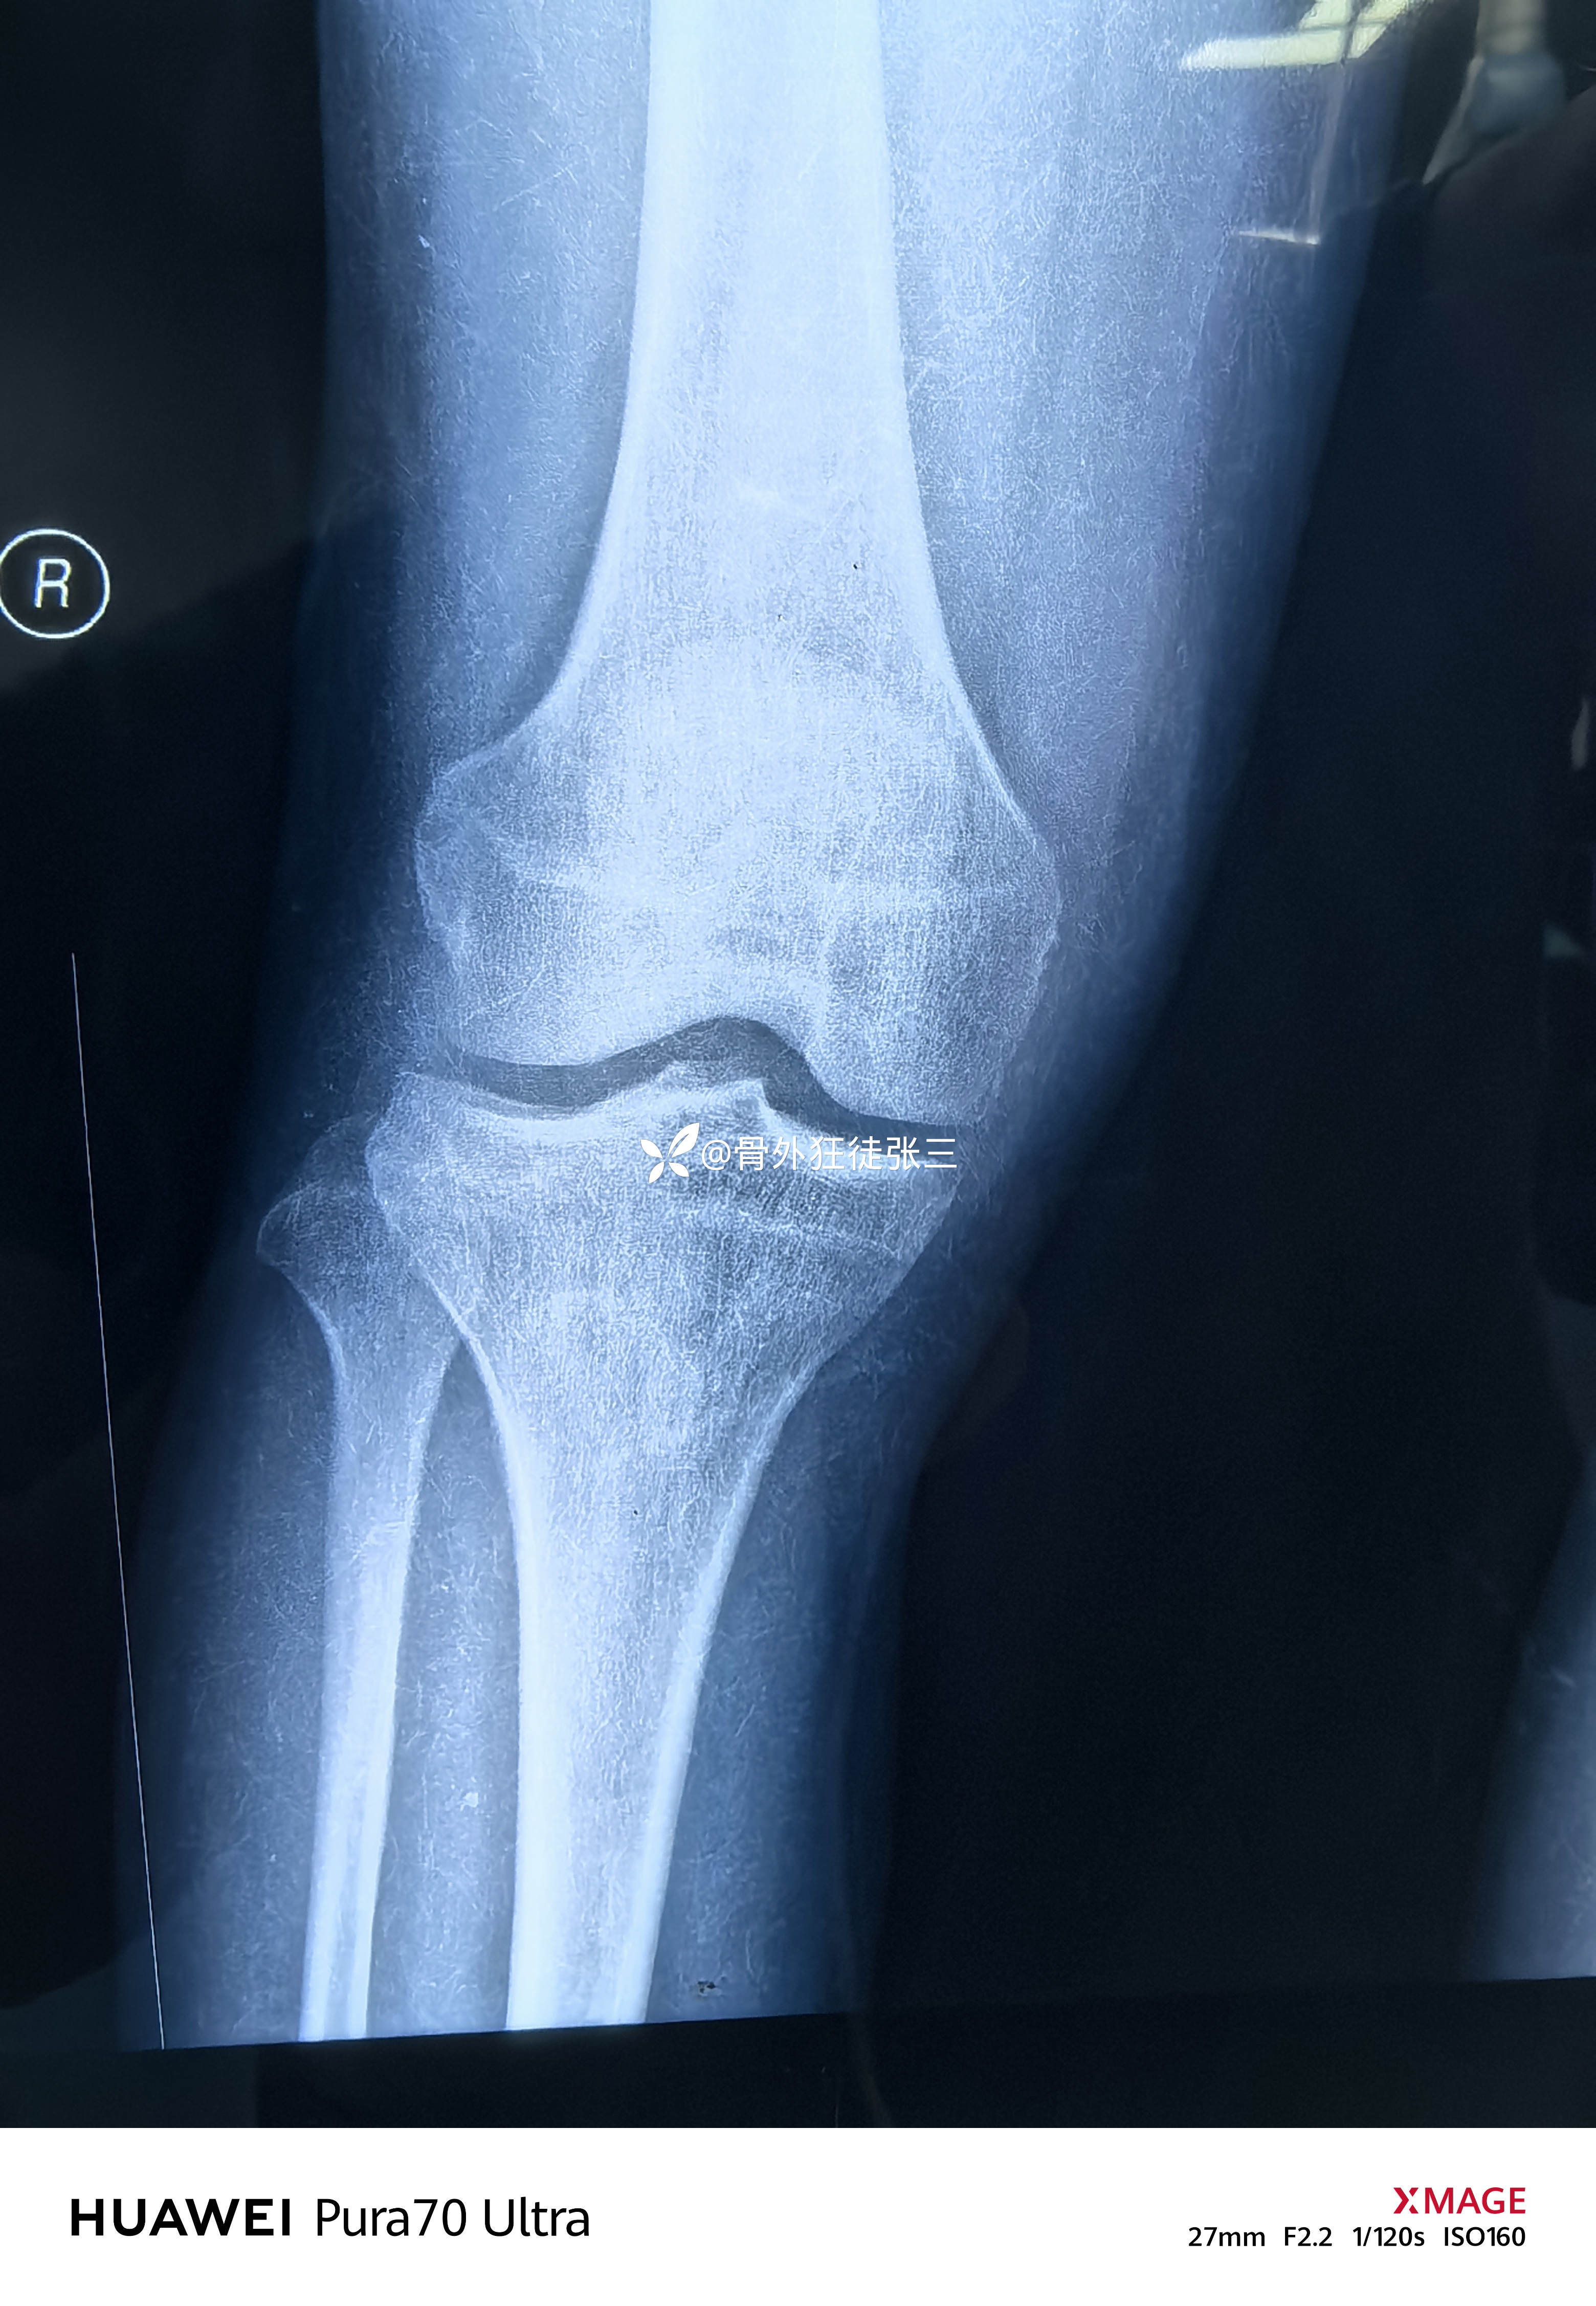

虽然X线平平无奇

右胫骨平台骨折

(屈曲内翻型——后内侧平台骨折+外侧平台塌陷+ACL止点撕脱)